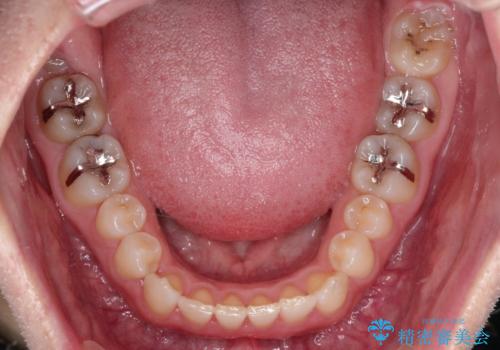

- 前歯の正中離開(すきっ歯)の改善を希望され来院された患者様です。

初診時の歯並びの状態としては、上顎中切歯間に1mm程の隙間があり、その他に見た目に関して気になるような問題点はない状態でした。

インビザライン(マウスピース)にて上顎のみの矯正治療を行いました。